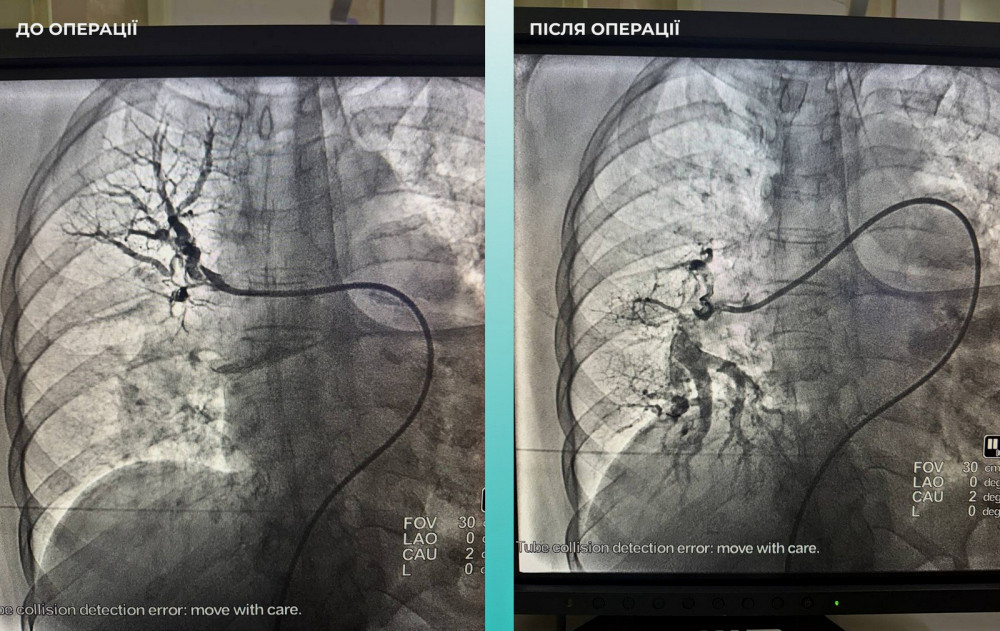

Кроме того, специалисты отметили, что пациентке тяжело дышать, что привело к дополнительному обследованию легких. Диагноз усложнился из-за тромбоэмболии легочной артерии.

Медицинская команда, состоящая из различных специалистов, приняла сложное, но крайне важное решение провести одновременную тромбоэктомию как мозговой, так и легочной артерий.

Операция прошла успешно. В настоящее время пациентка чувствует себя значительно лучше: она в сознании и уже может двигать конечностями.